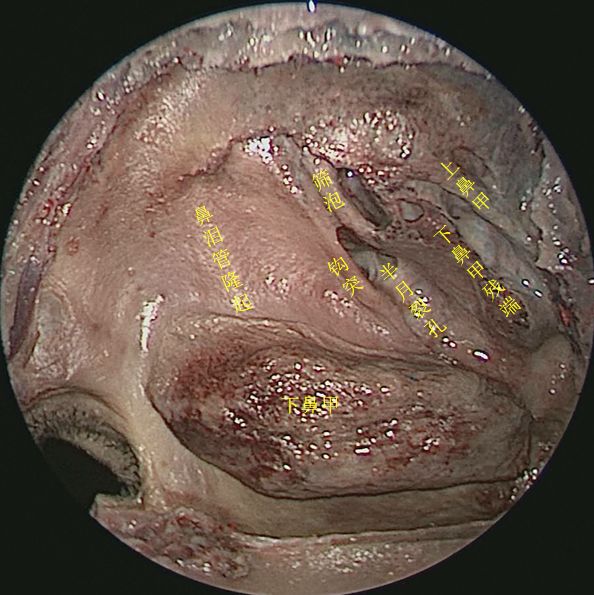

切除中鼻甲后观察鼻腔内整体空间形态

侧方观察右侧鼻腔侧壁结构

45度角观察右侧鼻腔侧壁